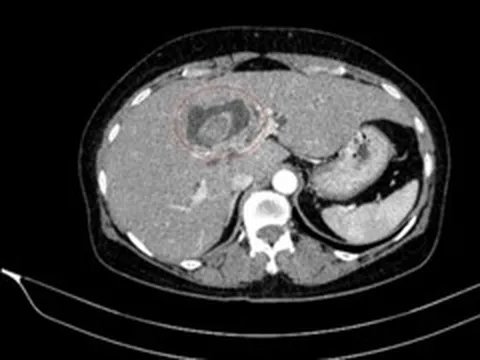

Ba người chết não hiến tặng 31 mô tạng, hồi sinh cho nhiều bệnh nhân 0

Cuối tuần qua, BV Việt Đức thực hiện liên tiếp ca lấy ghép tạng từ 3 người chết não, mang lại sự sống cho 8 bệnh nhân, cải thiện sức khỏe cho 6 người khác.